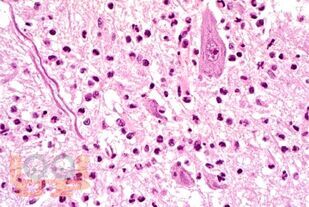

В учебном пособии представлены современные сведения об этиологии, эпидемиологии, основных аспектах патогенеза, клинических проявлениях, диагностике, дифференциальной диагностике, лечении и профилактике энтеровирусных неполиомиелитных инфекций.